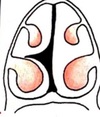

11

Q

Que arteria se encuentra afectada

A

ACA